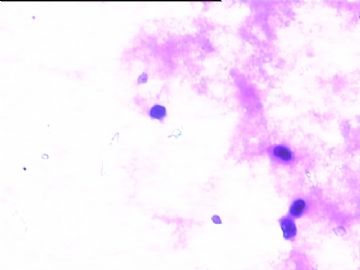

78y,男,胸水。 大家看看那些小于淋巴细胞的东东。

但,最后一图的组织细胞内吞噬现象,怎么解释。

离体的细胞在一定的时间内还是活细胞,所以我推测吞噬细胞可能还是有一定的吞噬功能的。不过,确实也不能就排除了在活体内的微生物感染的可能。结合临床应该能够得到一定程度的澄清。